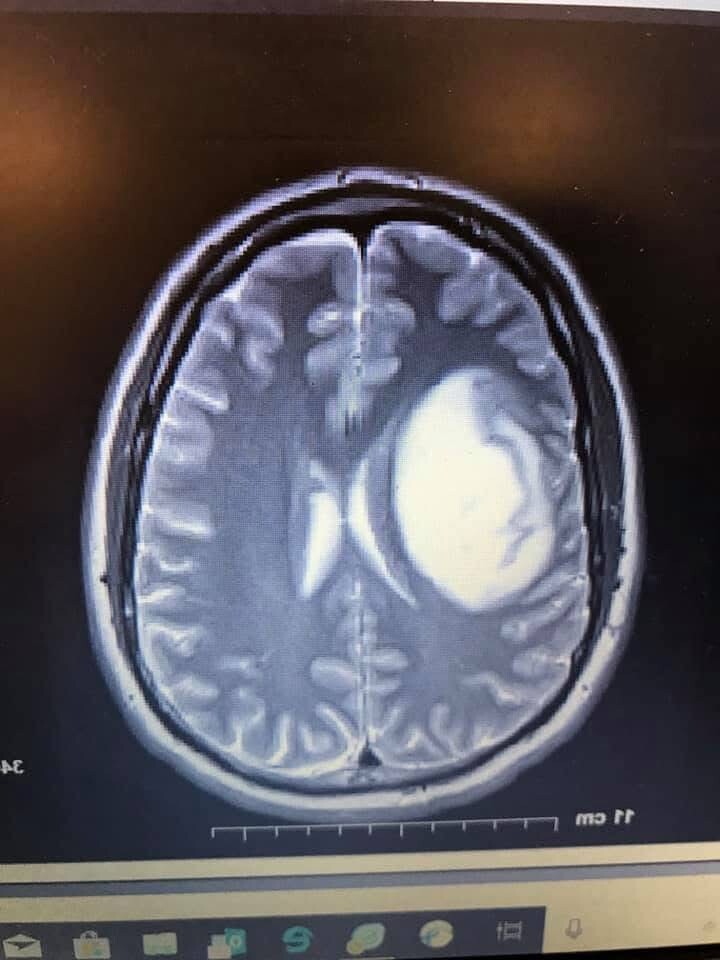

If you know Owen, you know he’d be the first to jump in and give anything that’s needed to help someone out, and the last to ask for help for himself. Now it’s our turn to help him. As you may have read on his Caring Bridge page (link below), he has been battling aggressive brain cancer since 2019, and despite multiple rounds of surgery, radiation and chemo, was recently given a heartbreaking prognosis of 6-10 months. His care team, along with Danielle, his wife and tireless supporter, are working hard with Owen to prepare for another round of radiation and a renewed focus on treatments and lifestyle changes that give him the quality of life he deserves.